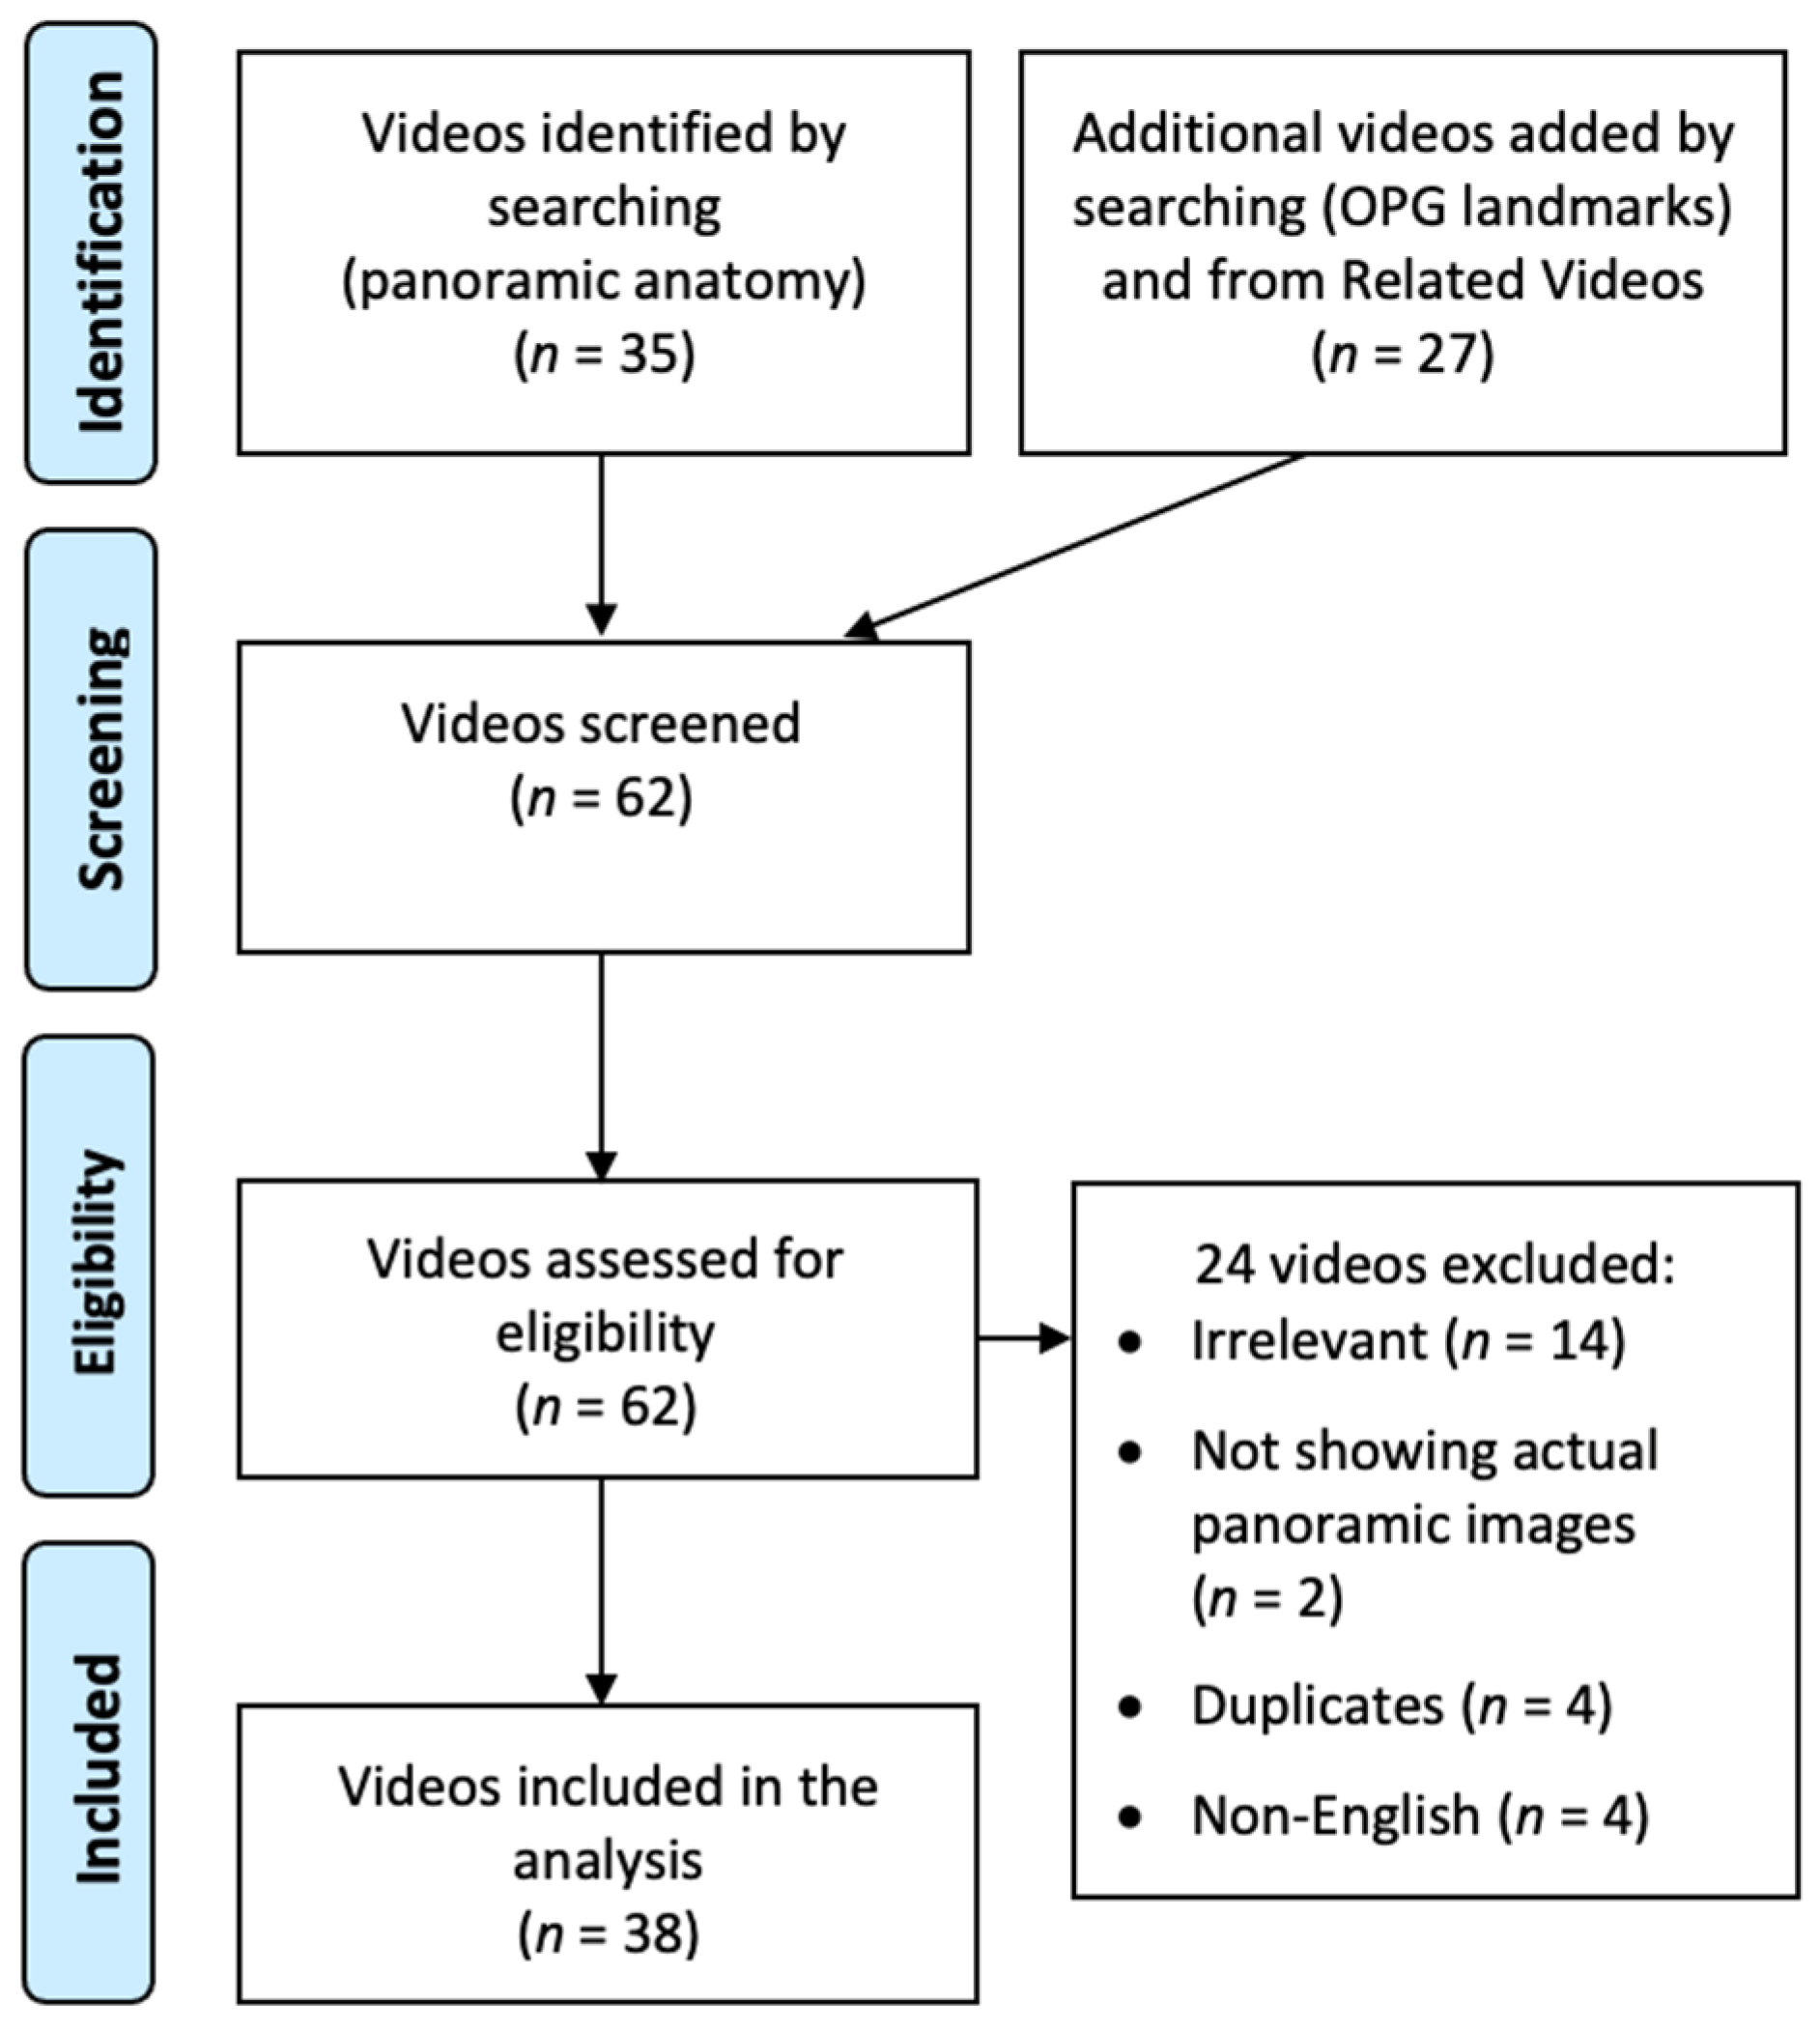

2. Materials and Methods

3. Results